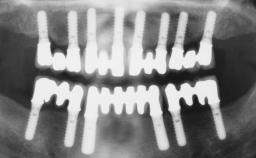

Rehabilitating an Edentulous Maxilla with a Fixed Dental Prosthesis Following Provisional Immediate Loading

This case features the flapless computer-guided placement of 7 bone-level implants, distributed to provide maximal support for the prosthetic framework. A rigid one-piece metallic framework was utilized as an interim restoration to reduce the risk of fracture associated with this prosthetic design. As part of the clinical examination, the SAC Assessment Tool was used, resulting in a surgical and restorative risk classification as “complex”.

# of Implants 7

Type of Implants Two-Piece

Guided Surgery Yes

Modality 6+ implants with immediate loading